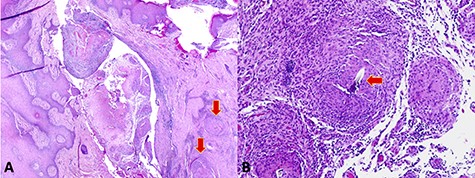

(A) Low-power microscopy image demonstrating a skin tract containing necrotic material and surrounding granulomas (arrows). (B) High-power microscopy image showing suture material embedded in the granulomatous tissue (arrow).